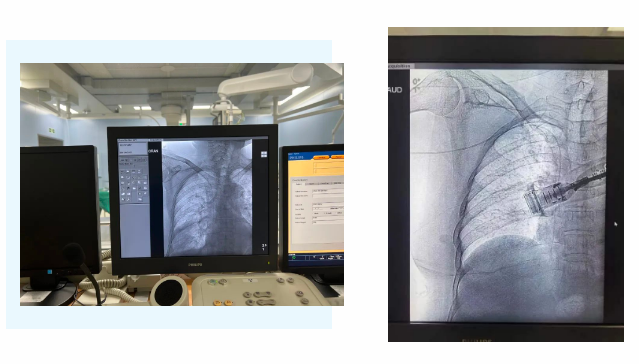

在麻醉手術(shù)中心的配合下,手術(shù)首先由韓海靜護(hù)士長在超聲引導(dǎo)下應(yīng)用“塞丁格”法穿刺將針尖一樣細(xì)的導(dǎo)絲送入血管,術(shù)中在DSA透視下將導(dǎo)管沿著血管送達(dá)上腔靜脈,尖端精準(zhǔn)定位至上腔靜脈開口處。隨后,胸腔外科支亞男主治醫(yī)師在穿刺點(diǎn)下方取2厘米小切口內(nèi)進(jìn)行上臂港囊袋和隧道的制作及導(dǎo)管與港座連接,最后進(jìn)行港體埋植及皮內(nèi)縫合,使患者切口隱蔽美觀創(chuàng)傷小,術(shù)中出血量極少。手術(shù)在X片影像留影,最終手術(shù)順利完成。